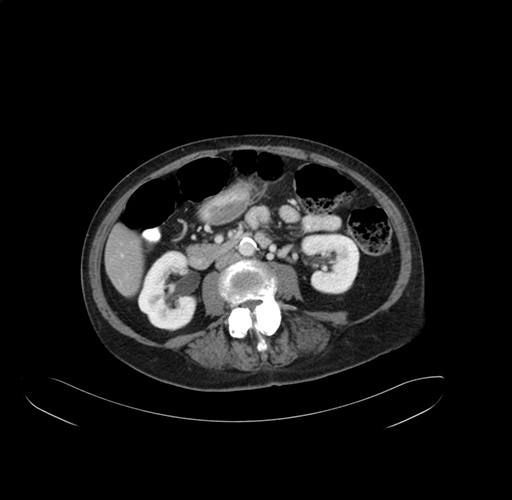

Pre-Chemo: Axial Venous

Axial Venous